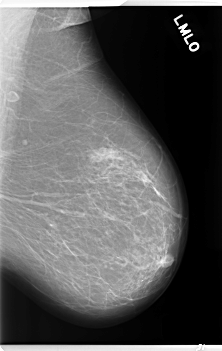

C_0253_1.LEFT_MLO

LEFT_MLO LINES 5960 PIXELS_PER_LINE 3768 BITS_PER_PIXEL 12 RESOLUTION 50 NON_OVERLAY